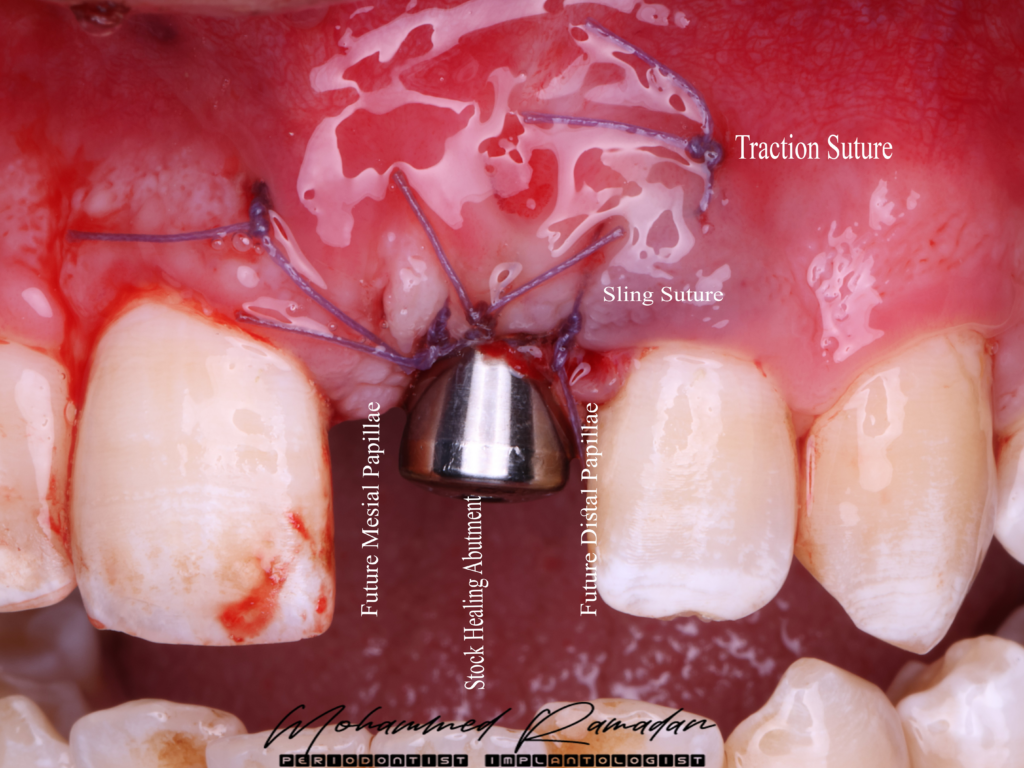

- Sub-epithelial connective tissue graft (CTG) placed via tunnel approach.

- Temporization achieved with a stock abutment, followed by a full-contour milled PMMA crown to promote papilla formation.